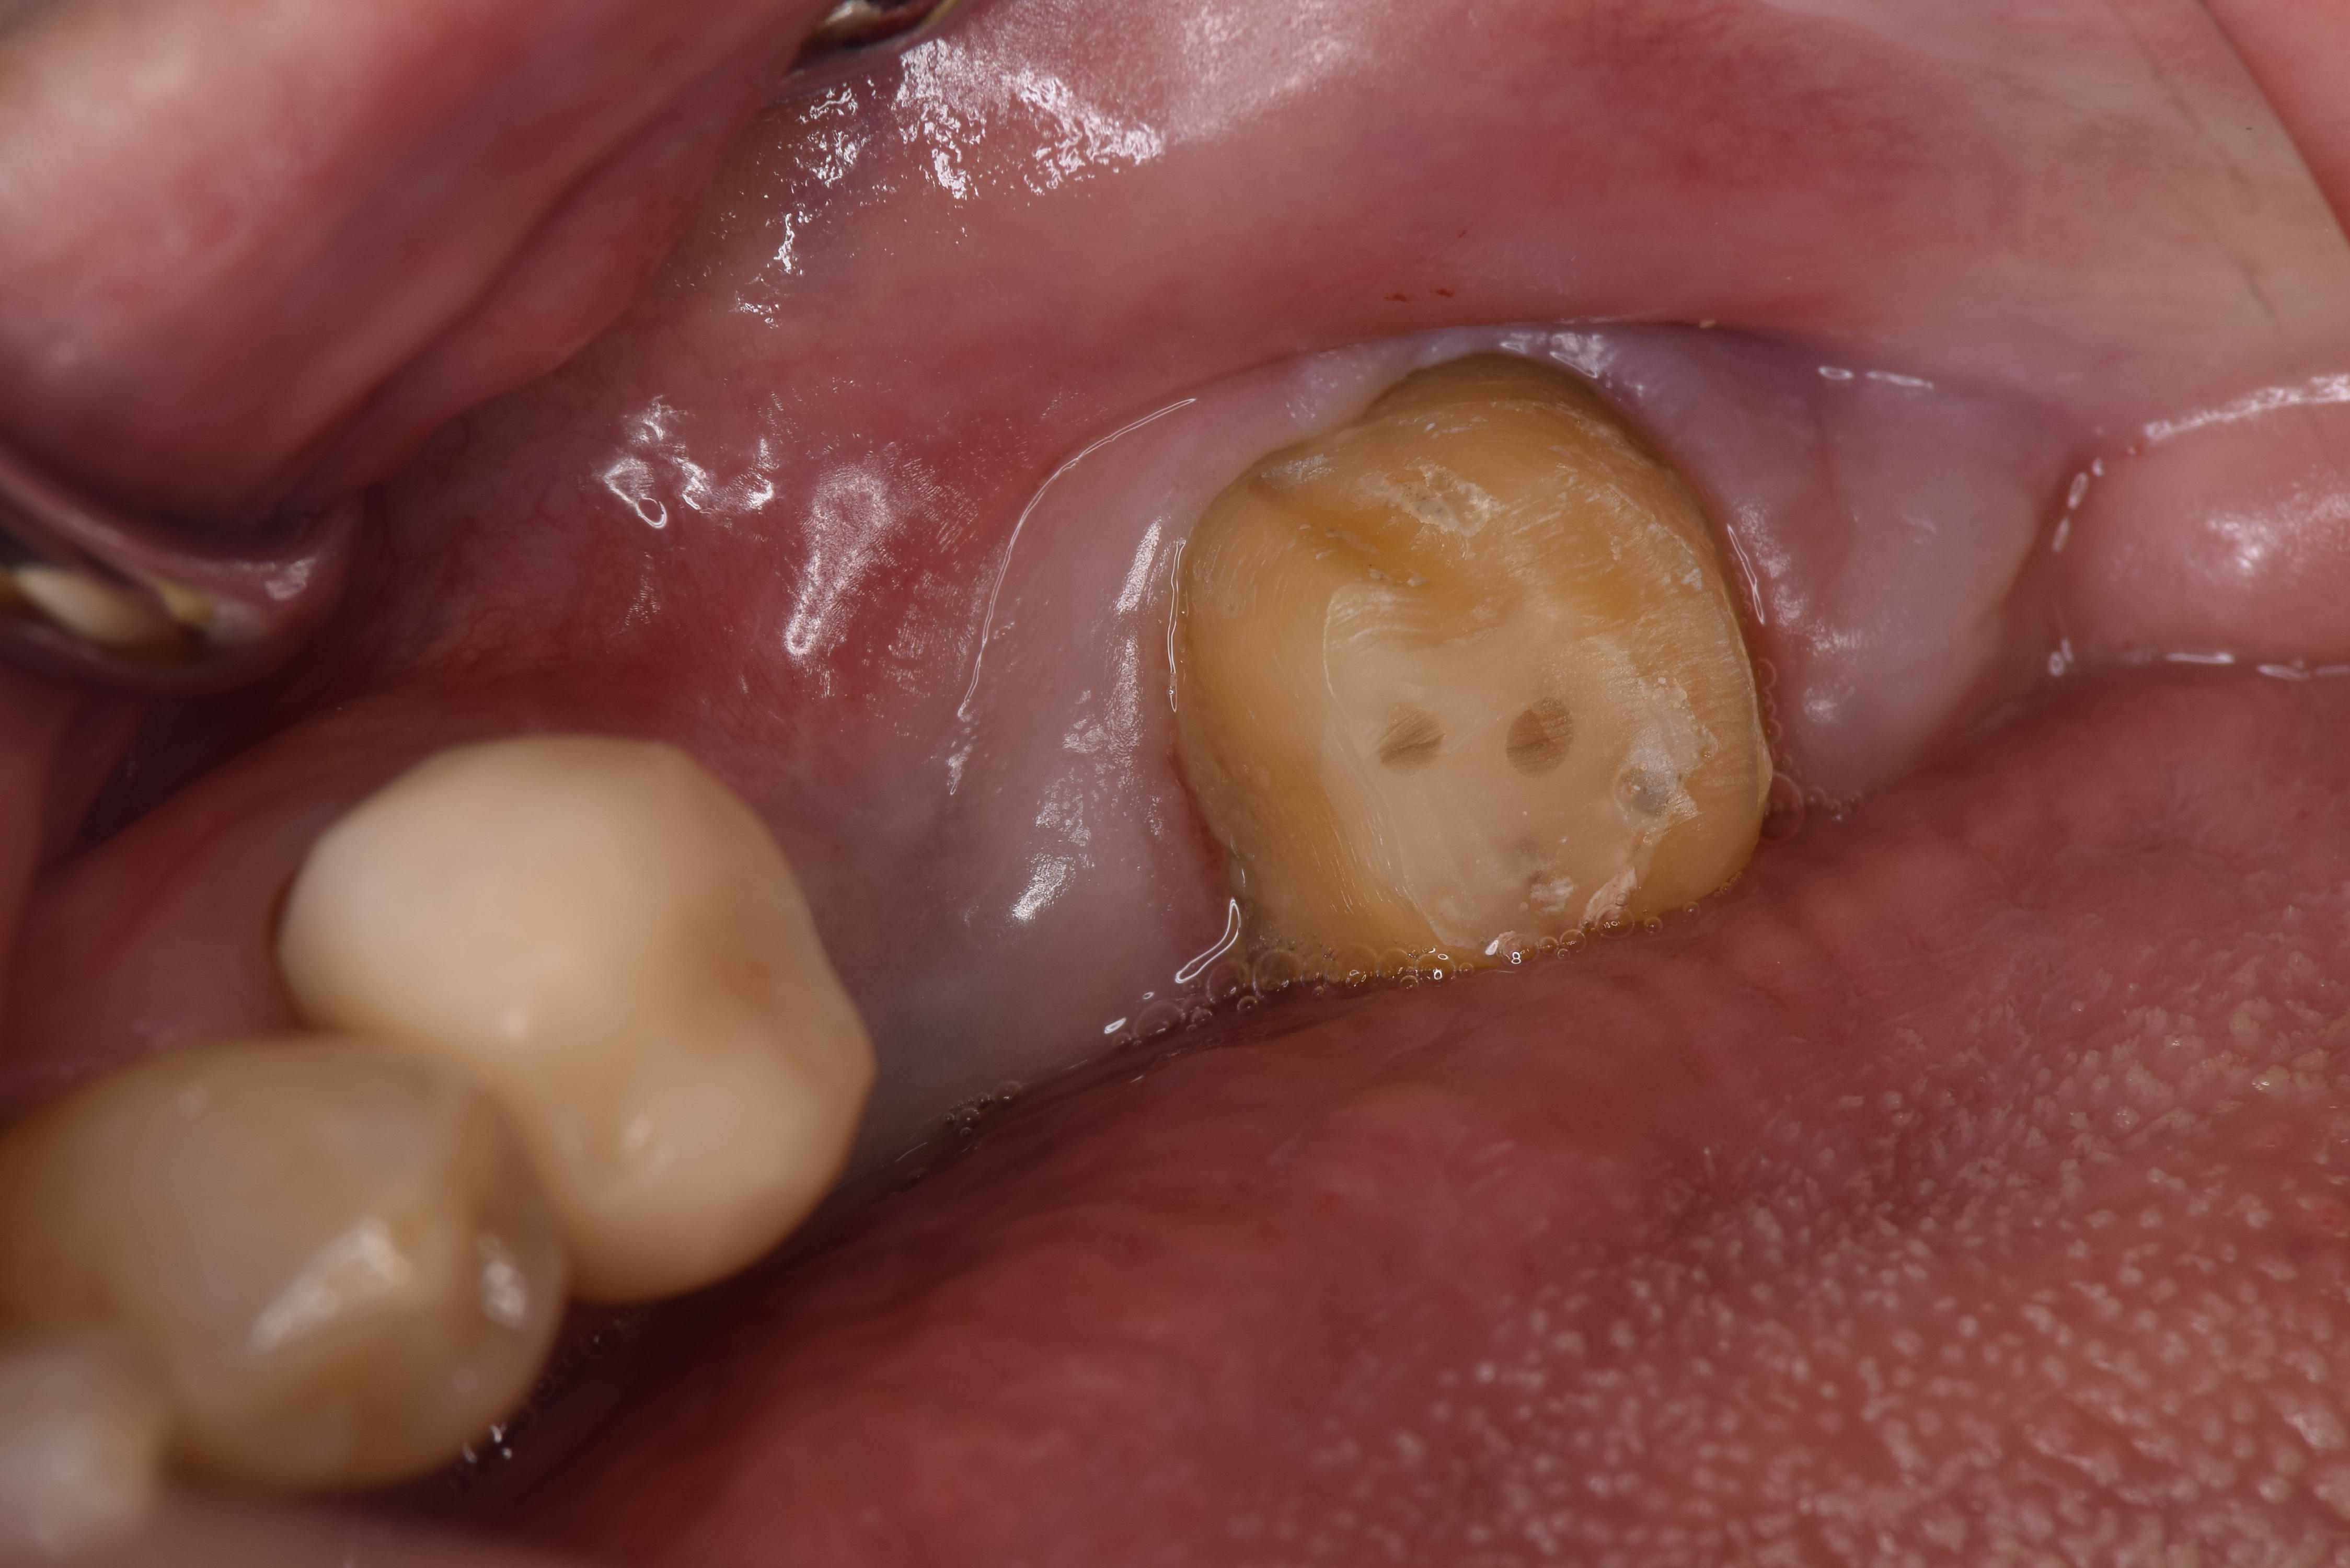

今回のケースでは左下7番が悪くなっていました(写真はミラー像)

実際に歯を抜いてみると、歯の周りに黒い歯石が大量についていました。これを除去していきます。

歯石を完全に除去しました。歯根端切除術も同時に行っています。